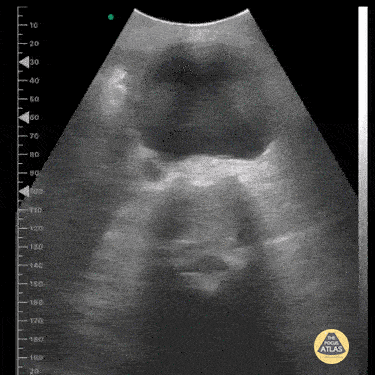

This image was taken from a pocket wireless device in the mesogastric region. We can see the short-axis aorta with its increased diameter and neighboring anatomical references such as the dorsal spine and inferior vena cava laterally. Image courtesy of Dr. Renato Tambelli